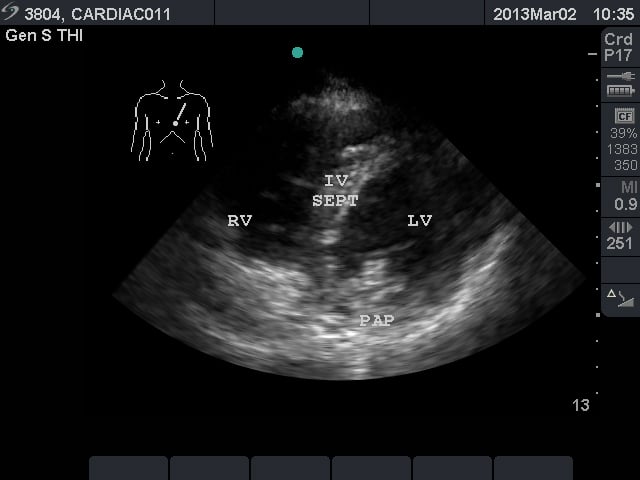

Video 2. Normal parasternal long axis view - Parasternal Short Axis View: This view is a cross sectional view of the left and right sides of the heart. These can be “sliced” at various levels between the base and the apex. By fanning the probe towards the right shoulder, one can visualize the aortic valve in cross section. The “Mercedes Benz” sign shows all three of the leaflets. The right ventricular outflow tract and pulmonary valve can be seen in this view. At the base, the mitral valve is seen inside the left ventricle. At the mid ventricular level, the papillary muscles are seen within the left ventricle. This is the most commonly used parasternal short axis view in point-of-care ultrasound in the acute care setting. At the apex, the left ventricle has tapered and no structures are seen within.

- Figure 3. Parasternal short axis view at the mid ventricular level. RV = right ventricle. IV SEPT = interventricular septum